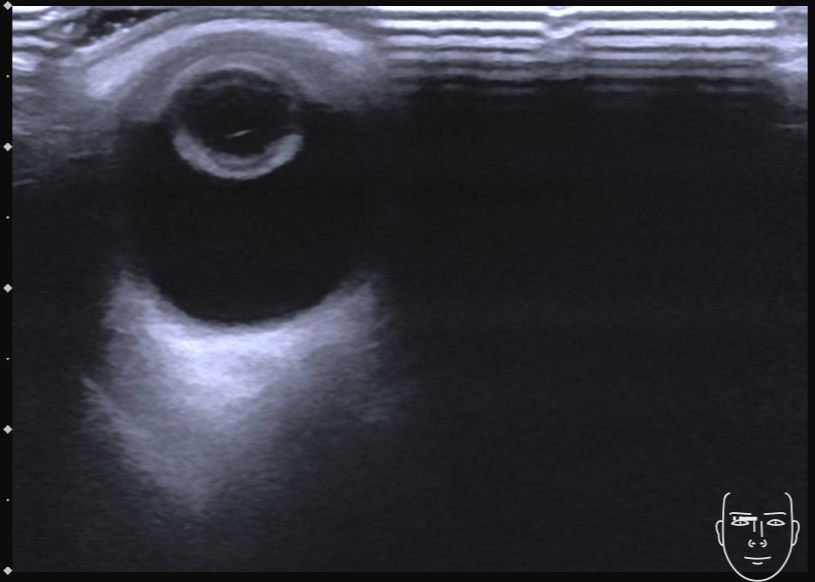

图 1 晶状体混浊初发期

图片来源:作者提供